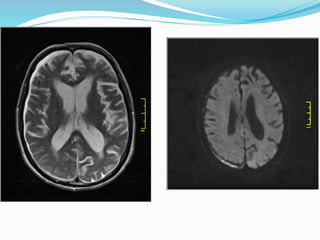

MRI

 Can distinguish between acute ,chronic & subacute subdural hematoma

 MRI

 The appearance of a haematoma varies with the biochemical state of

haemoglobin which varies with the age of the haematoma. The most

sensitive standard sequence is FLAIR.

 Hyperacute

 T1: isointense to grey matter

 T2: iso to hyperintense

 FLAIR: hyperintense to CSF

 Acute

 T1: iso- to hypointense to grey matter

 T2: hypointense to grey matter



 Subacute

 T1: typically hyperintense

 T2: variable appearance usually hyperintense

 FLAIR: hyperintense

MRI  Can distinguishbetween acute ,chronic & subacute subdural hematoma  MRI  The appearance of a haematoma varies with the biochemical state of haemoglobin which varies with the age of the haematoma. The most sensitive standard sequence is FLAIR.  Hyperacute  T1: isointense to grey matter  T2: iso to hyperintense  FLAIR: hyperintense to CSF  Acute  T1: iso- to hypointense to grey matter  T2: hypointense to grey matter  FLAIR: hyperintense to CSF 

 Subacute  T1:typically hyperintense  T2: variable appearance usually hyperintense  FLAIR: hyperintense